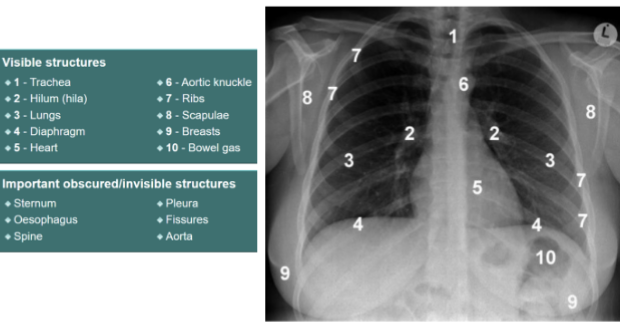

Label this CXR (10 things)

1) trachea 2) hilum- should have R and L 3) lungs 4) diaphragm 5) heart 6) aortic knuckle 7) ribs 8) scapulae 9) breasts 10) bowel gas

Identify trachei, bronchi, aortic nuckle

yes

Idenfity R + L hila

Identify cardiophrenic angle, R + L hemidiaphragms, stomach bubble, liver, spleen

identify hemi diagrams (2) and stomach bubble

identify costophrenic angles

Identify costophrenic angles (post + ant)

Identify soft tissues/what are you looking for?

nipples